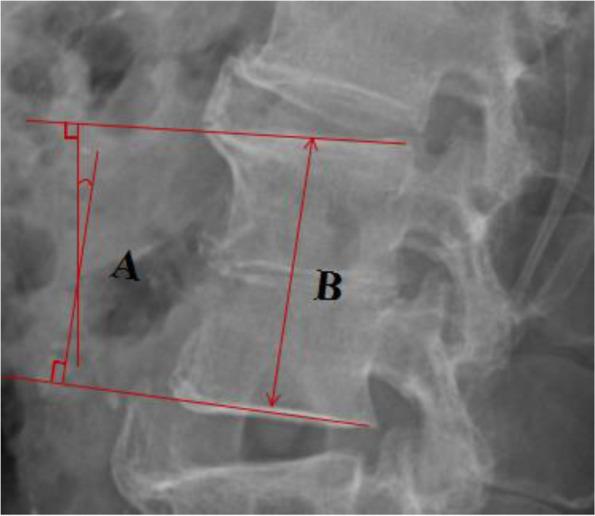

The mean follow-up period of time was 14.8 months. The average operative time and intra-operative blood loss were 129.0 ± 19.76 min and 309.2 ± 92.96 mL, respectively. No severe intra-operative complications were observed during surgery, except in 1 case that develops abdominal pain and distension after surgery, 2 cases that develop left-sided transient thigh pain/numbness and 8 cases that complains of donor site (iliac crest) pain. All of these symptoms disappeared 8 weeks after surgery. Tissue sample cultures were obtained from all patients intraoperatively and four (33.3%) were positive, including 2 with Staphylococcus aureus, 1 with Staphylococcus epidermidis, and 1 with Escherichia coli. During an average of 22.5 ± 2.1 days (range, 14-29 days) after surgery, WBC, CPR, and ESR levels in all patients had returned to normal. All patients were pain free with no recurring infection. Solid bony fusions were observed in all cases within 6 months, including 10 with I grade fusion, 2 with II grade fusion according to the classification suggested by Burkus et al. No fixation failure was observed during follow up and solid bony fusions were observed in all 12 patients at finally follow-up. A significant postoperative increase was also observed in the mean segmental height and lordosis (P < 0.05), followed by a slight decrease of segmental height and lordosis at final follow-up. At the final follow up, the mean VAS (1.5 ± 0.6) and ODI (18.9 ± 7.6) were significantly lower than VAS (8.4 ± 2.7) and ODI (71.2 ± 16.5) before surgery (P < 0.01).

平均随访时间为 14.8 个月。手术时间和术中出血量分别为 129.0 ± 19.76min 和 309.2 ± 92.96mL。术中除 1 例术后出现腹痛腹胀、2 例左侧一过性大腿疼痛/麻木和 8 例供区(髂嵴)疼痛外,无严重术中并发症。所有症状均在术后 8 周消失。所有患者术中均取组织样本培养,其中 4 例(33.3%)培养阳性,包括 2 例金黄色葡萄球菌、1 例表皮葡萄球菌和 1 例大肠杆菌。术后平均 22.5 ± 2.1 天(14-29 天)内,所有患者的白细胞计数(WBC)、C 反应蛋白(CRP)和红细胞沉降率(ESR)均恢复正常。所有患者均无疼痛,无感染复发。所有患者在 6 个月内均获得了坚固的骨性融合,根据 Burkus 等人的分类,其中 10 例为 I 级融合,2 例为 II 级融合。随访过程中未发现固定失败,12 例患者最终随访时均获得了坚固的骨性融合。术后节段高度和脊柱前凸也显著增加(P<0.05),最终随访时节段高度和脊柱前凸略有下降。最终随访时,VAS(1.5±0.6)和 ODI(18.9±7.6)均显著低于术前的 VAS(8.4±2.7)和 ODI(71.2±16.5)(P<0.01)。